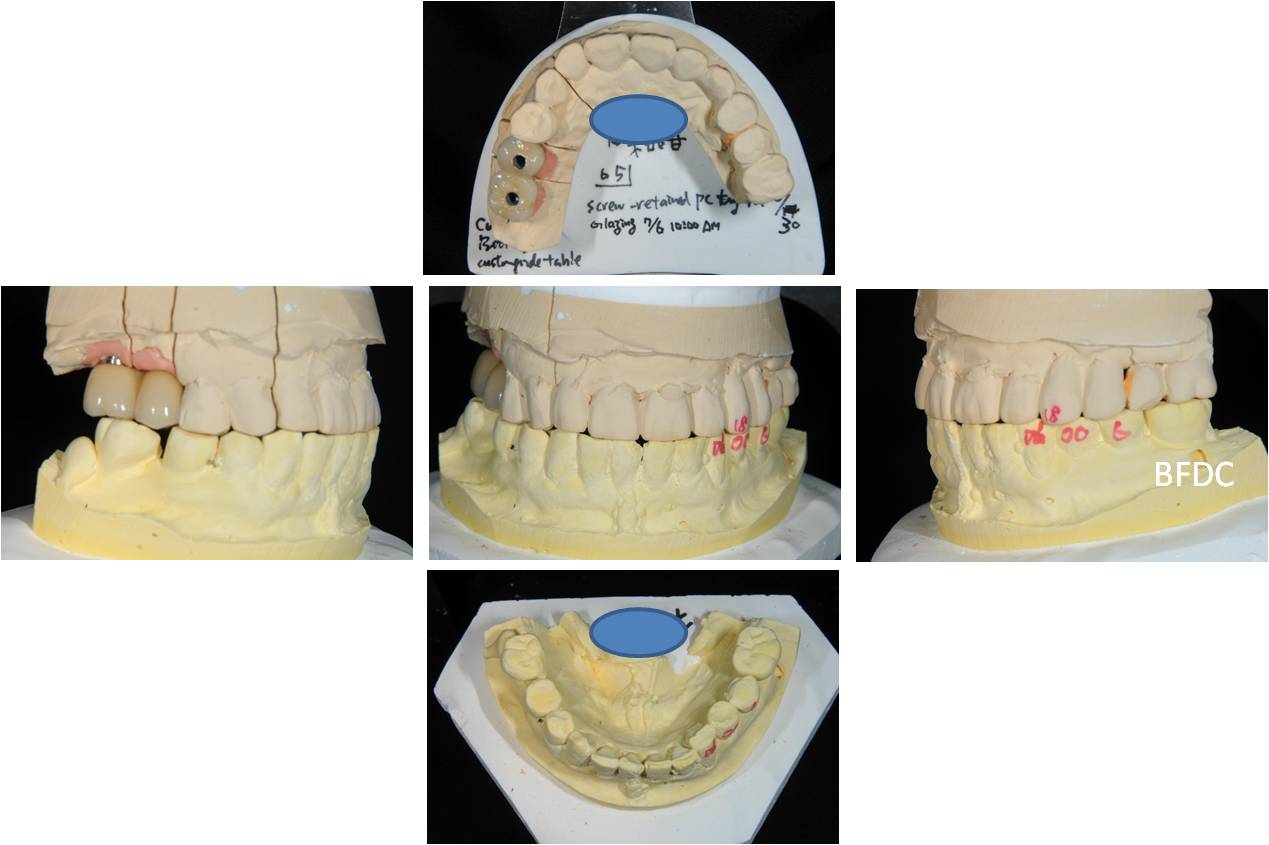

咬合器工作模型

全瓷冠模型